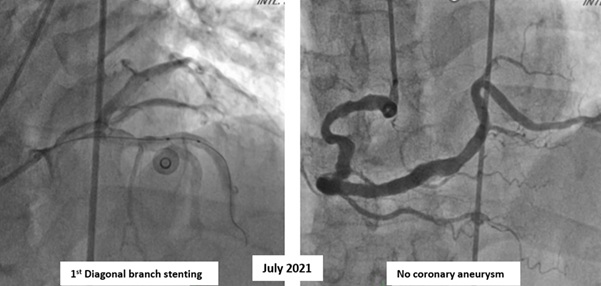

The coronary angiography showed a giant right coronary artery (RCA) aneurysm with total occlusion at mid-RCA and collateral flow from the left circumflex artery. It is different with right coronary angiography at 4 years ago that showed no coronary aneurysm. The left coronary artery has a good flow to the distal without any significant stenosis and patent stent on 1st diagonal artery branch.